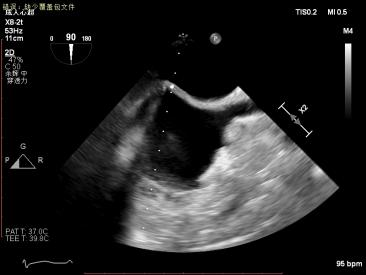

1.四腔心切面和二腔心切面可见左室高侧壁室壁瘤形成,二尖瓣瓣叶脱垂伴重度反流。

2.X-plane切面调整瓣膜夹的位置:主要定位PISIA最明显的A2/P2区,分别二尖瓣交界联合切面和 LVOT切面调整夹子轴向,同时在3D切面上观察夹子方位和区域,瓣膜夹位置良好,轴向和方位均理想后,捕获A2/P2偏1区处的前后瓣叶,逐渐关闭瓣膜夹,TEE显示二尖瓣反流明显减轻至微量,3D视角显示组织桥连续完整,瓣叶抓捕稳定。彩色血流提示微量的瓣膜反流,测量平均跨瓣压差3mmHg,复查左上肺静脉血流频谱恢复正向,手术效果理想,逐步释放瓣膜夹系统撤出体外。